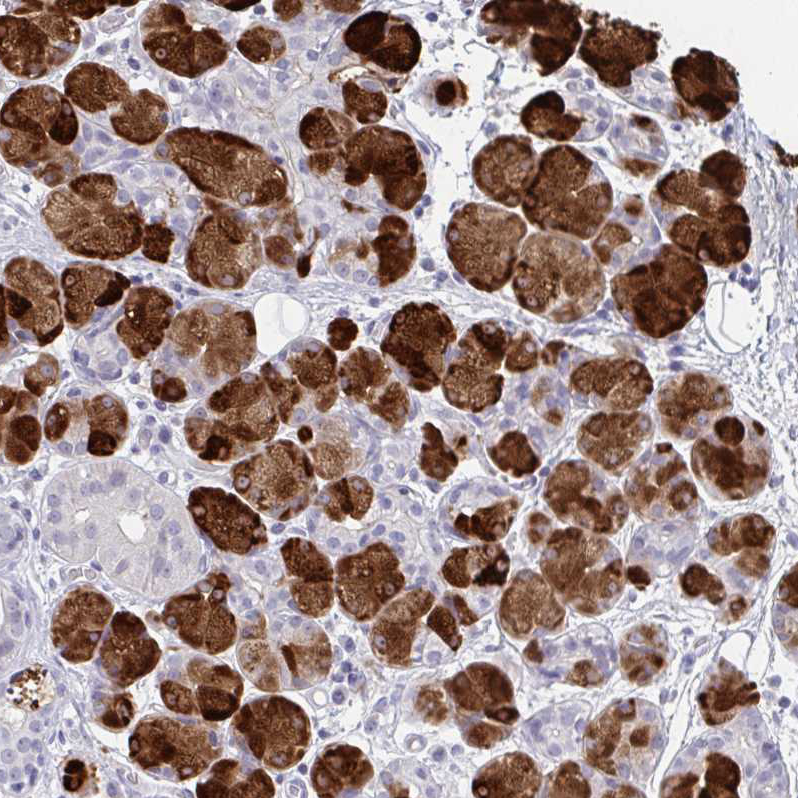

Immunohistochemical staining of human salivary gland shows strong cytoplasmic positivity in glandular cells.